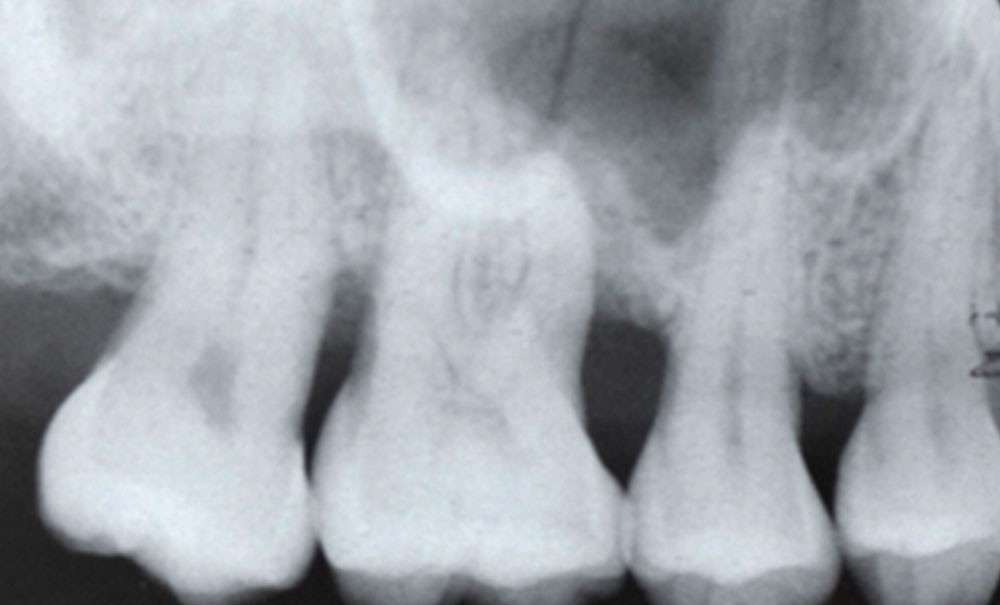

La classification des maladies et affections parodontales et péri-implantaires du World Workshop de Chicago de 2017 propose un système de diagnostic des parodontites basé sur 4 stades et 3 grades de maladie. Ce système vise à établir un lien entre la classification de la parodontite et les approches préventives et thérapeutiques, dans le sens où elle ne décrit pas seulement la sévérité et l’étendue de l’affection, mais aussi le degré de complexité de sa prise en charge rapporté au profil de risque individuel du patient [1].

La Fédération Européenne de Parodontologie (EFP) a organisé en 2019 un European Workshop of Periodontology (EWP) dédié à formaliser des recommandations cliniques qui, en se basant sur la littérature la plus récente et probante, puissent traiter des différentes étapes cliniques dans la prise en charge des parodontites de stades I, II et III. Quinze revues systématiques et méta-analyses constituent le support de ce travail de recommandations. Chaque recommandation proposée a été discutée et votée jusqu’à avoir un consensus des experts participants, précisément 90 experts européens en parodontologie, 36 représentants des Sociétés Savantes de Parodontologie de l’Union européenne, des représentants extra-européens (Amérique du Nord) et une méthodologiste.

L’objectif principal de ce travail est de promouvoir la meilleure prise en charge possible des patients atteints d’une parodontite grâce à l’application de protocoles de soins standardisés, personnalisés et evidence-based. Améliorer la qualité du traitement des parodontites signifie aussi réduire les conséquences de cette maladie chronique (par exemple, perte dentaire), améliorer la santé orale et générale des patients et aussi leur qualité de vie.